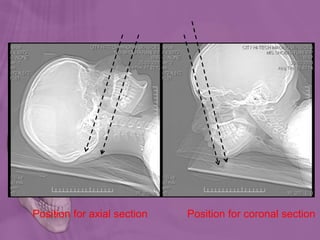

Position for axial section Position for coronal section